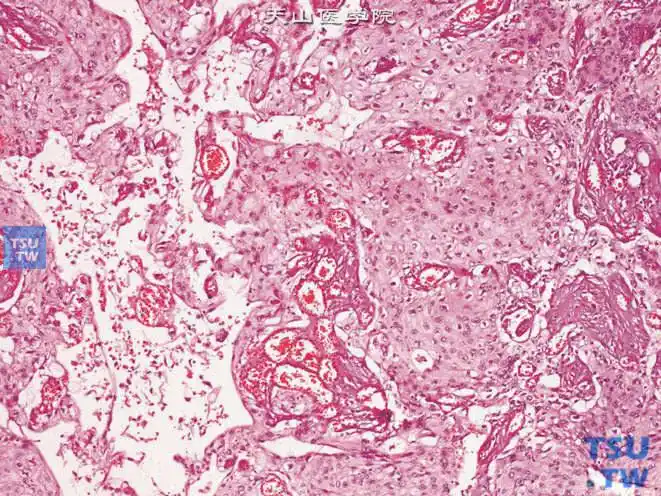

尿道鳞癌.可见细胞间桥